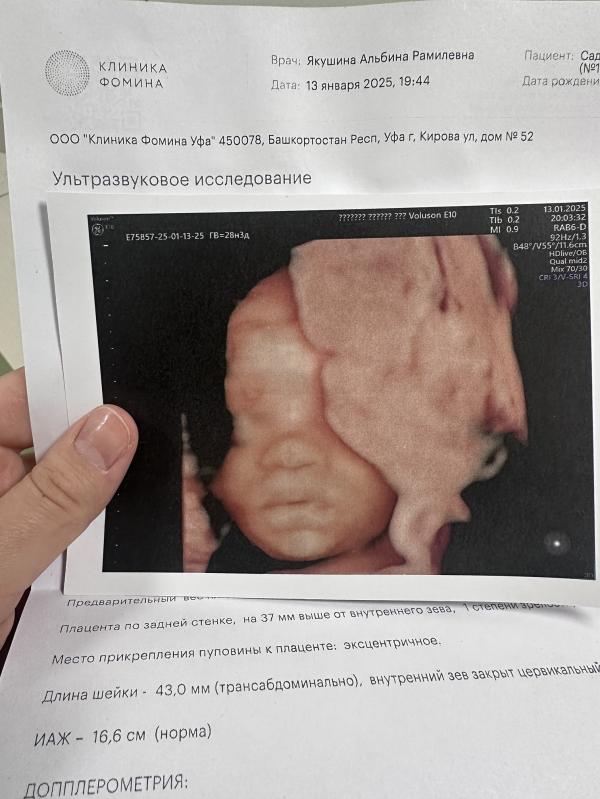

Хотя все в пределах нормы, не превышаем, не уменьшаем по сроку. Но увидев эти щечки, чутка испугалась🥲😁 Стараюсь держать диету) но как то не идеально конечно все. А дети каждый раз под 5кг. Но в те года я диету вовсе не держала, просто мне не говорили ничего. Надеюсь малышка все же будет в пределах 3-4кг🤍

Вес пока у малыша тоже в норме 675гр 😁 надеюсь на не крупного 🙈